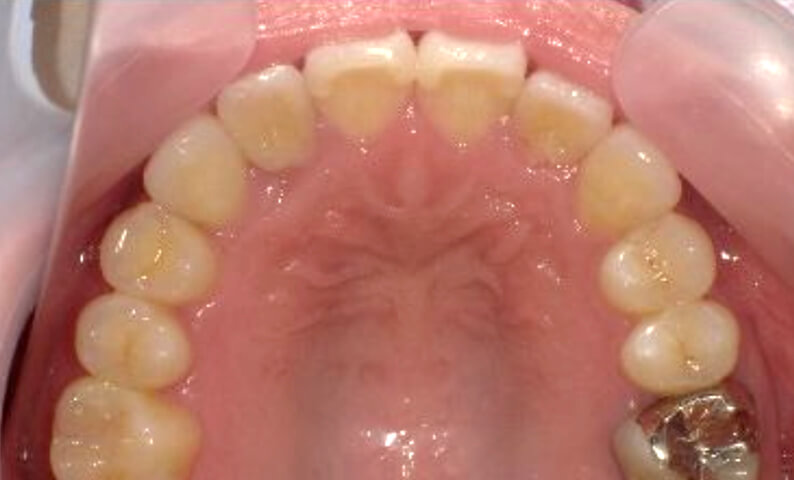

症例_022 上顎だけの部分矯正

治療期間:9ヶ月金額:30万円+税女性前歯のガタガタ前歯のガタガタ上の前歯だけ

| Before | After |

|---|---|

|